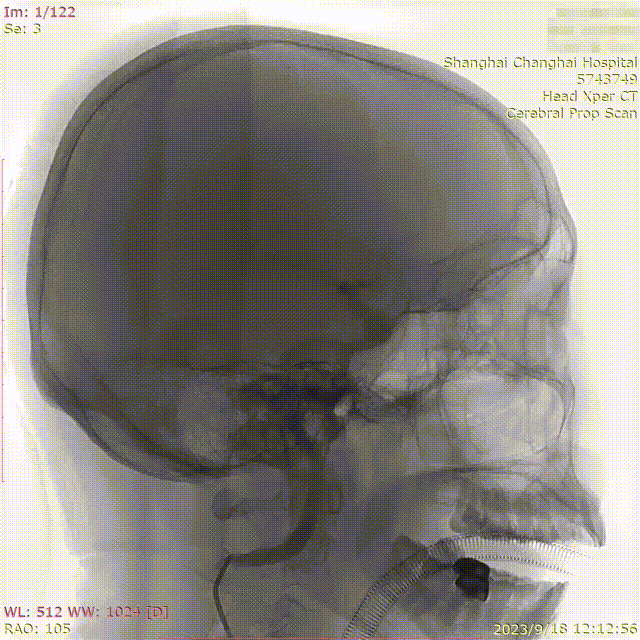

患者体检发现颅内动脉瘤,于3月前因出现右眼充血2次,同时逐渐出现视力减退,入外院就诊。排除眼科疾病,MR提示左枕叶亚急性脑梗死,同时发现左颈内动脉C6段动脉瘤,大小约7mm。

术前造影